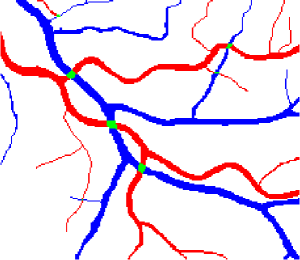

In this paper, we propose a coherence-penalized minimal path model, where the associated minimal paths favour to pass by a vessel that is located in the flatten region of an external feature map. We observe that along a piece of retinal vessel, the values of gray levels vary slowly. More specifically, retinal arteries have lower contrast of gray levels than veins due to the blood materials and imaging modality. In other words, in some extent the arteries and veins are distinguishable in terms of vesselness values. Such an observation can be used to solve the short branches problem that the minimal paths associated to a metric may pass through segments belonging to different vessels as shown in Figs. 1b and 1c. Fig. 1d shows the result from the proposed method, which can avoid such problem. Fig. 1a gives the artery-vein (AV) groundtruth. In this paper, we denote by blue and green dots the source and end points respectively.